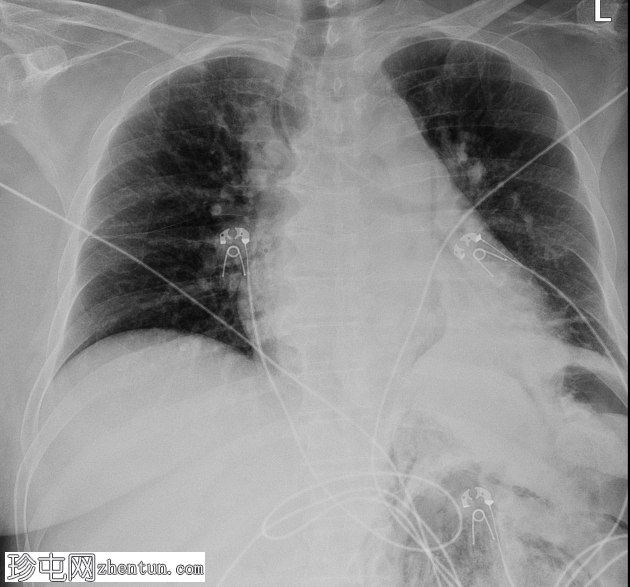

4.png

矢状位增强扫描(门静脉期)

左肾广泛破坏,伴有碎裂和气体膨胀

气体延伸至:

进入肾周间隙,伴有坏死碎屑

经肾后间隙进入腰大肌、腹膜前脂肪和体壁

进入肠系膜后间隙、肾后间隙、侧圆锥间隙和联合筋膜间隙,直至股鞘

环绕左侧肾上腺、胃和脾脏,并位于膈下

经食管裂孔和主动脉裂孔进入纵隔

气体勾勒出腹膜后间隙,这些间隙可作为潜在腔隙,同时也展示了免疫功能低下的老年女性如何被侵袭性感染突破组织屏障。股鞘是腹膜后间隙与下肢之间感染扩散的通道,食管裂孔和主动脉裂孔是腹膜后间隙与纵隔之间的通道。腹膜的突破使得少量气体进入腹腔,而腹横筋膜的突破则使感染扩散至后腹壁。